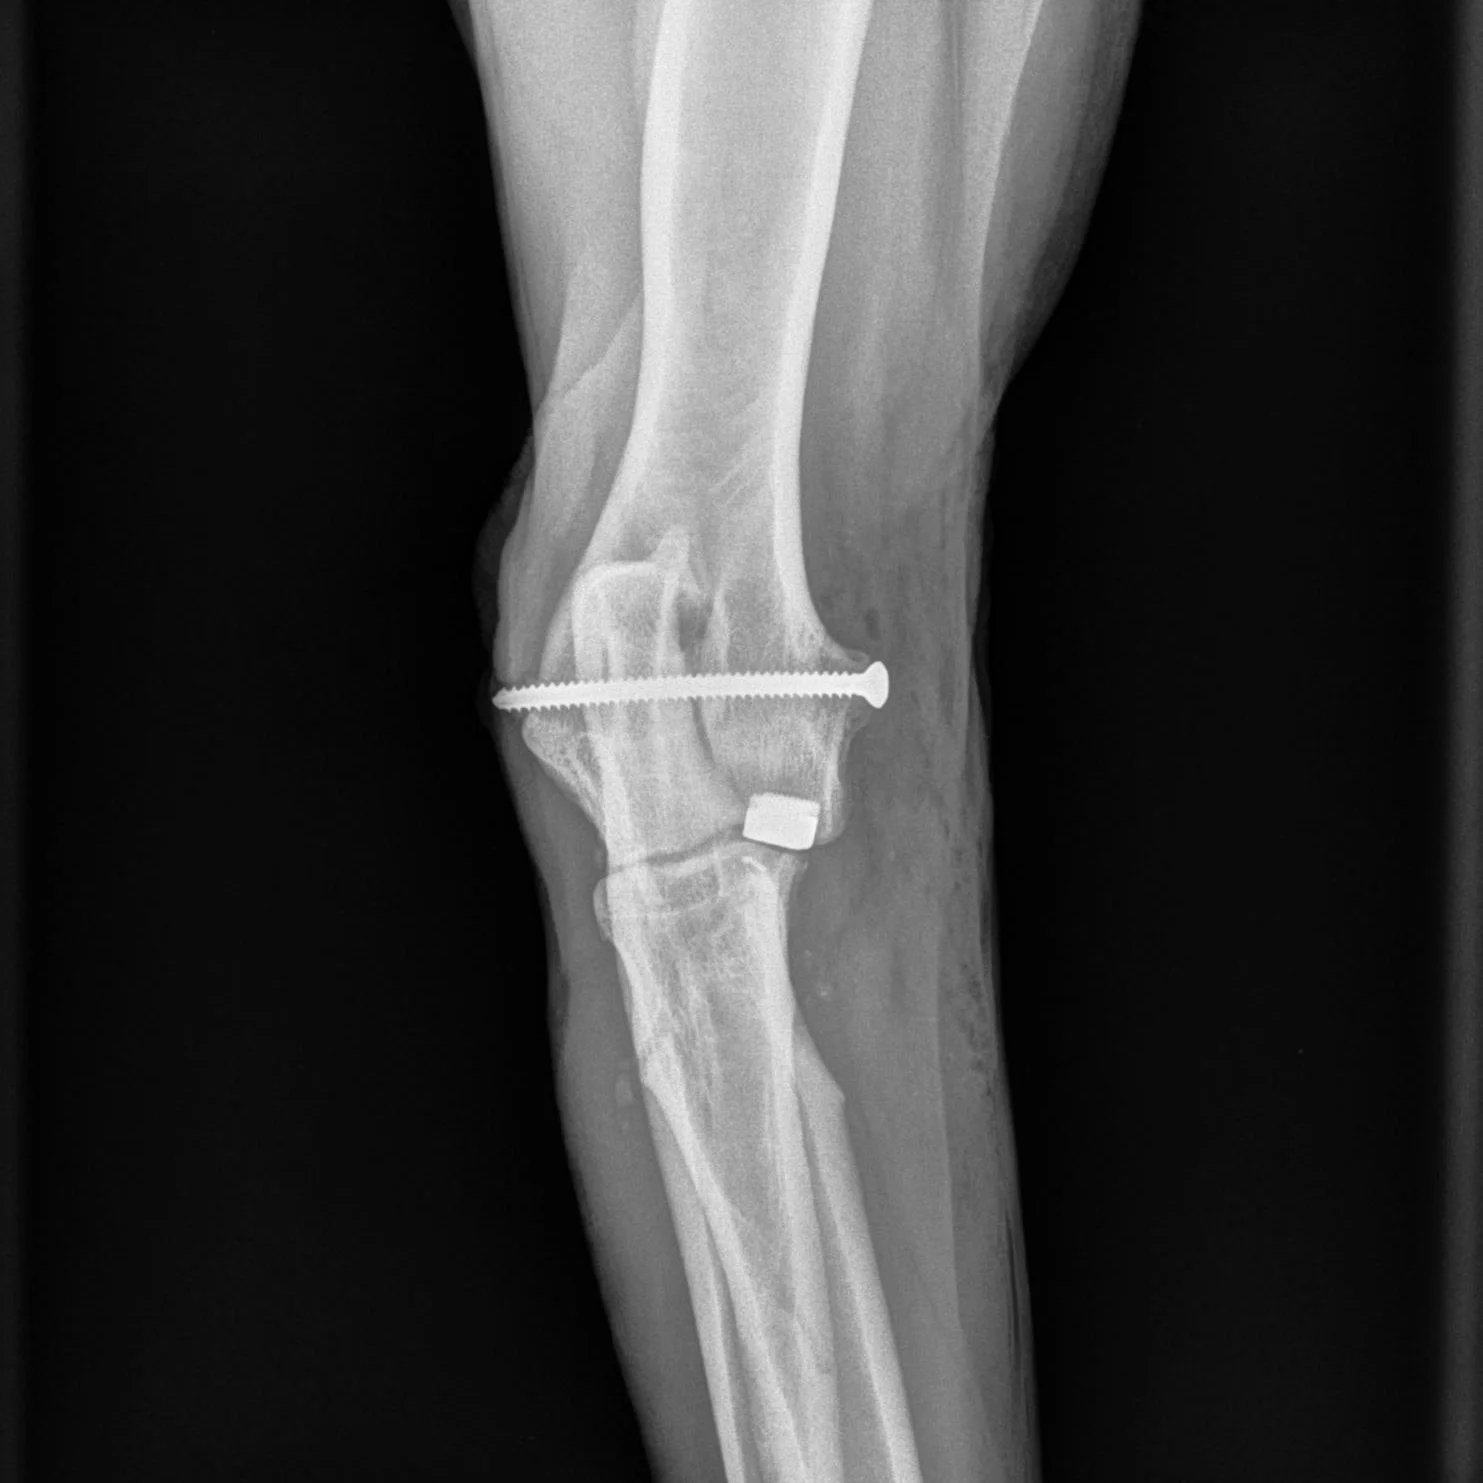

Op de plaats van de slijtage wordt een miniprothese in het gewricht aangebracht: